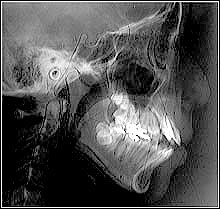

舌小帯と開咬

舌の運動機能障害

症例

永久歯が後ろから!?